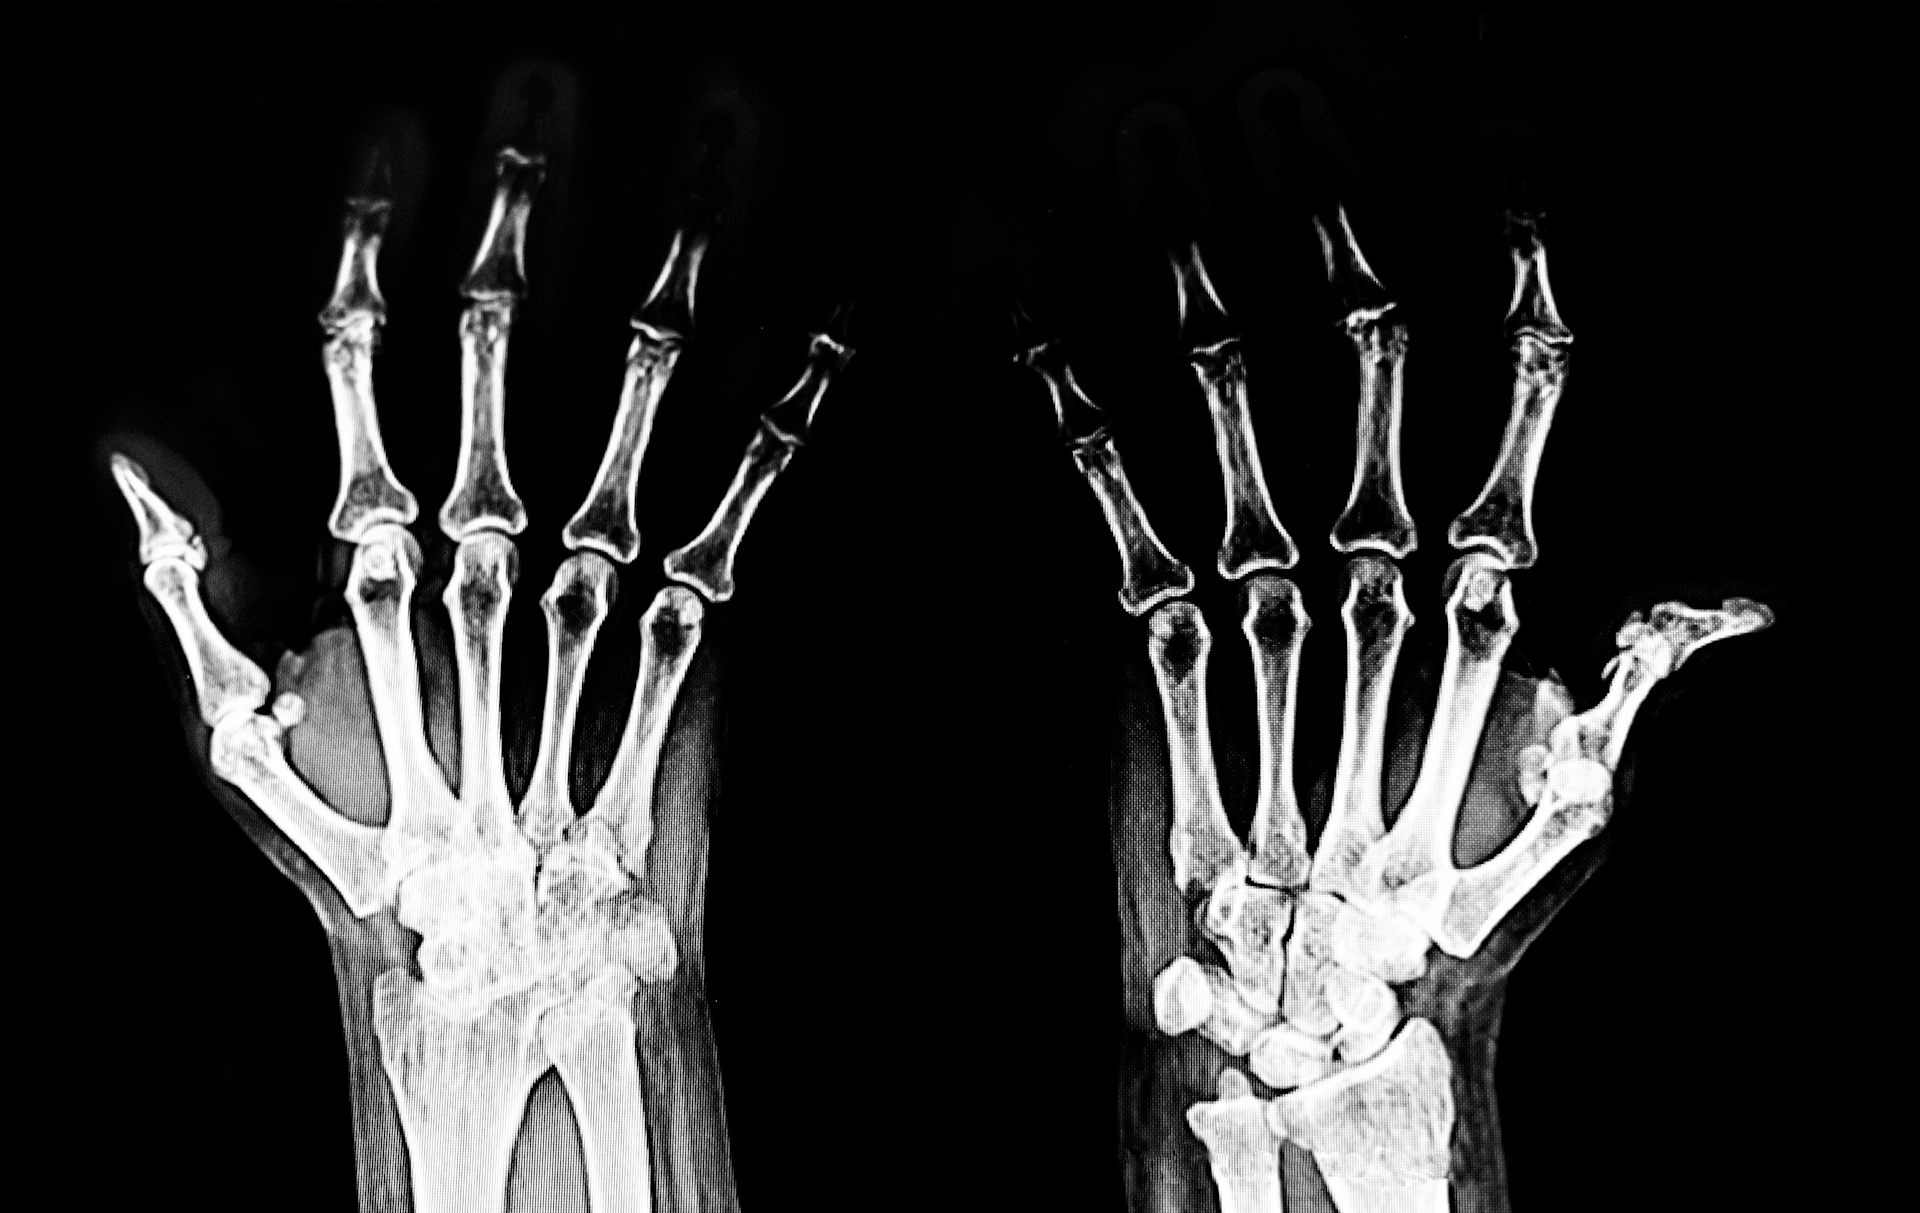

Rheumatoid arthritis is less common than osteoarthritis, affecting around 514,000 Australians. It mostly impacts the wrists and small joints in the hands and feet, though larger joints such as the elbows, shoulders, knees and ankles can also be involved.

As with osteoarthritis, your doctor will diagnose rheumatoid arthritis based on your symptoms and a physical exam.

Some other tests can be useful. Blood tests may pick up specific antibodies that indicate rheumatoid arthritis, although you can still have the condition with negative results.

X-rays may also reveal joint damage if the disease is advanced. If there is uncertainty, an ultrasound or MRI can help detect inflammation.